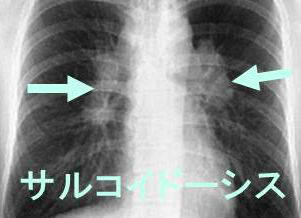

肺サルコイドーシスは、胸部X線で偶然に両側肺門リンパ節腫脹(BHL:bilateral hilar lymphadenopathy)で見つかるのが最も一般的(悪性リンパ腫でも同様に見えます)。両側肺門リンパ節腫脹(BHL)のみの場合は2年以内で80%が自然寛解。自然軽快しなければ間質性肺炎・肺線維症に進行。